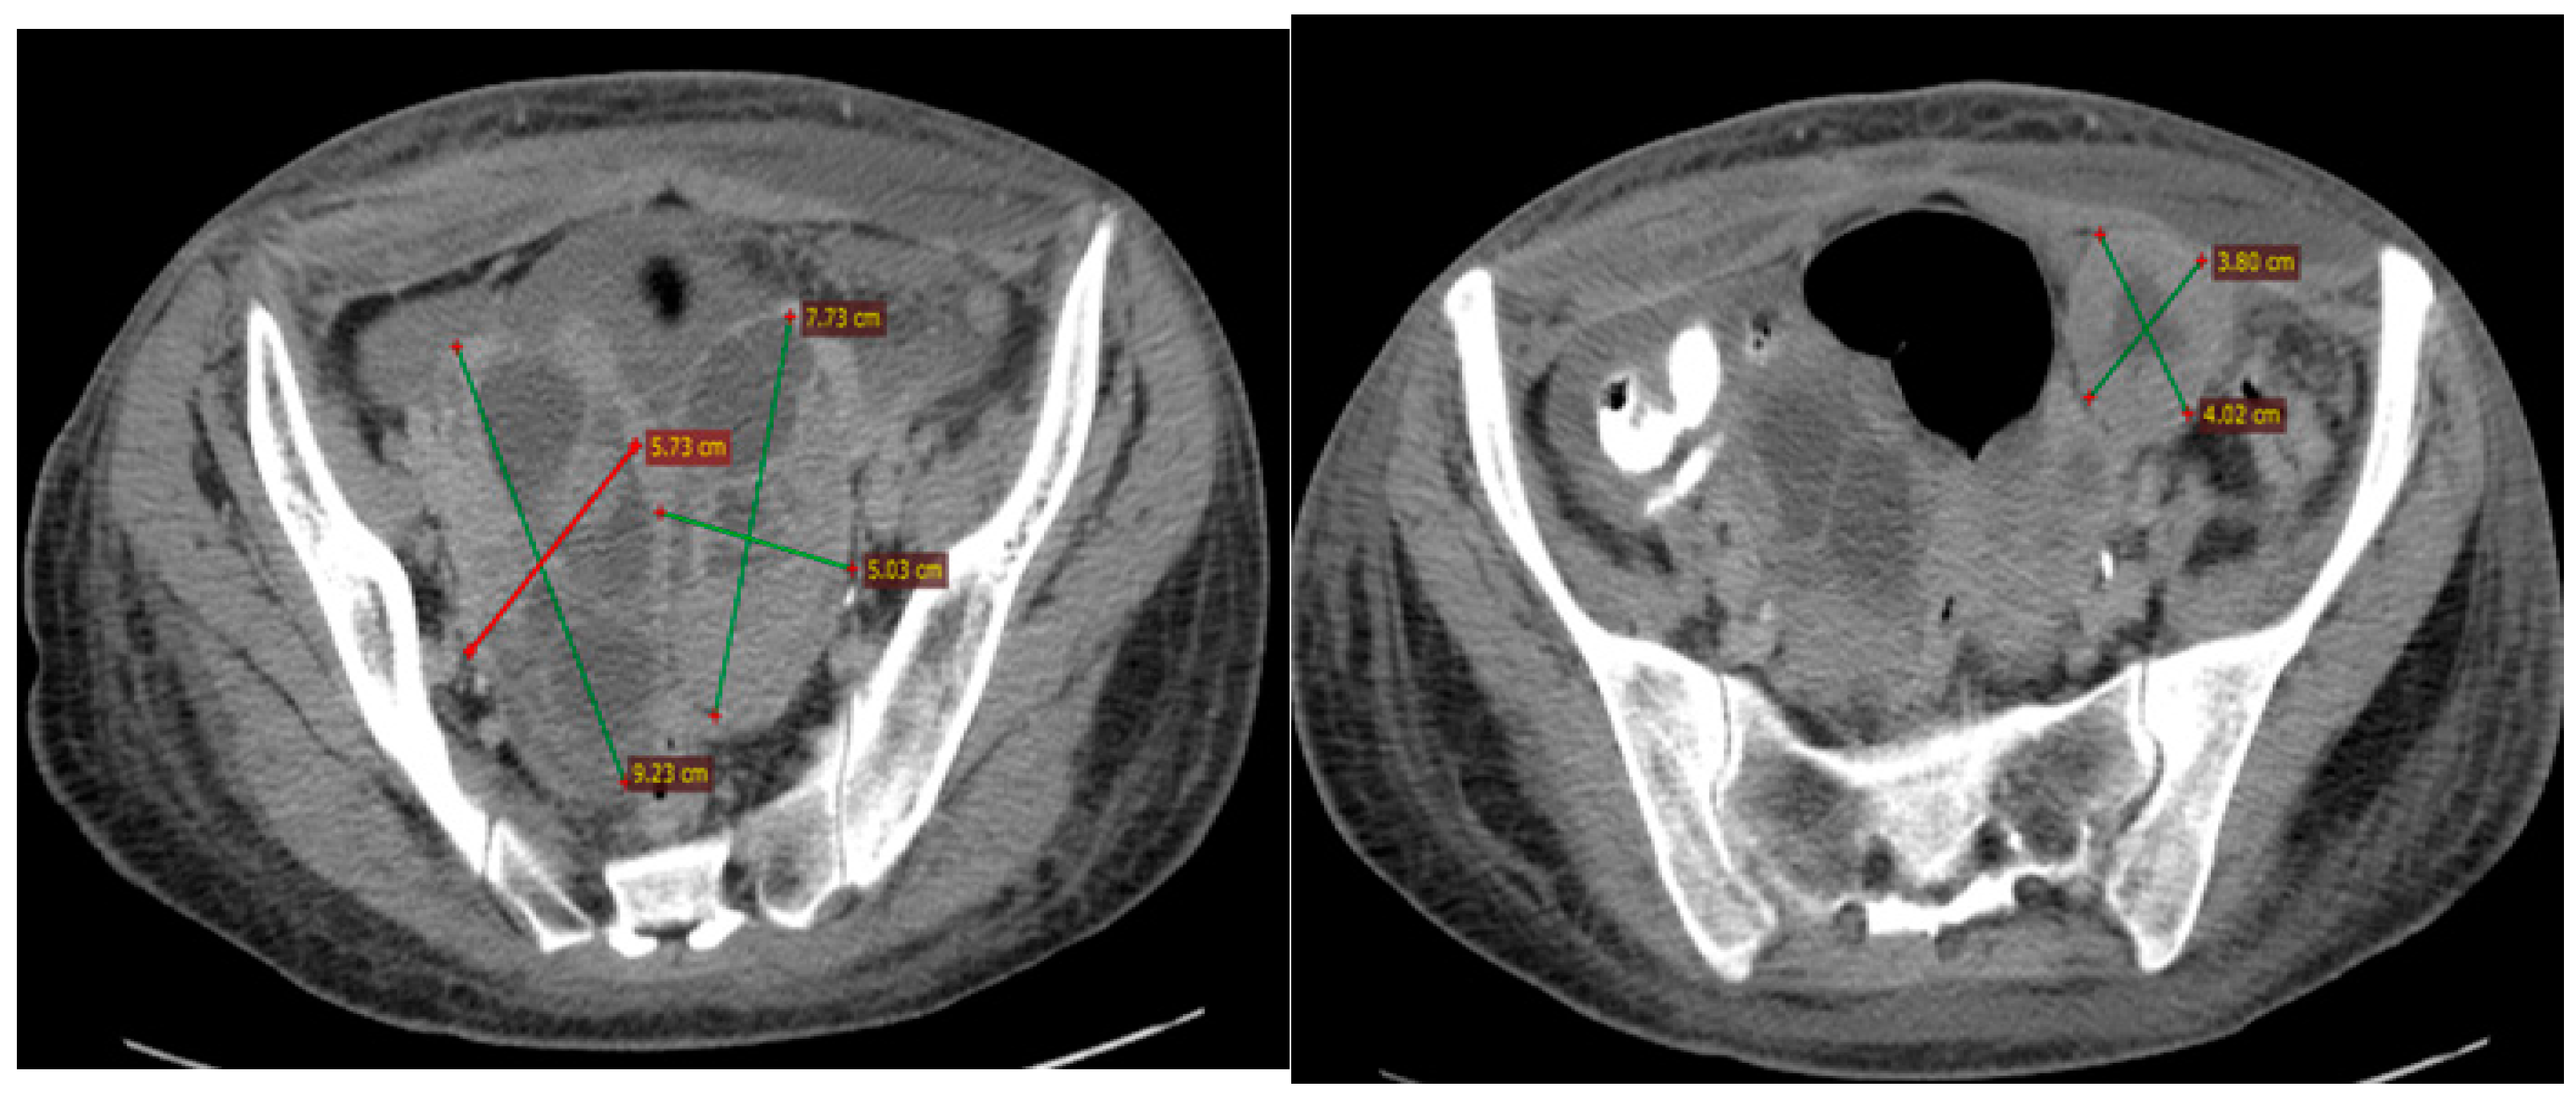

2.2.3. Examinations and Investigations

2.2.5. Treatment and Outcomes

2.2.6. Follow-Up